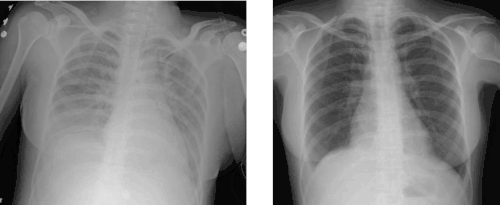

| Micrograph of diffuse alveolar damage, the histologic correlate of TRALI; H&E stain | |